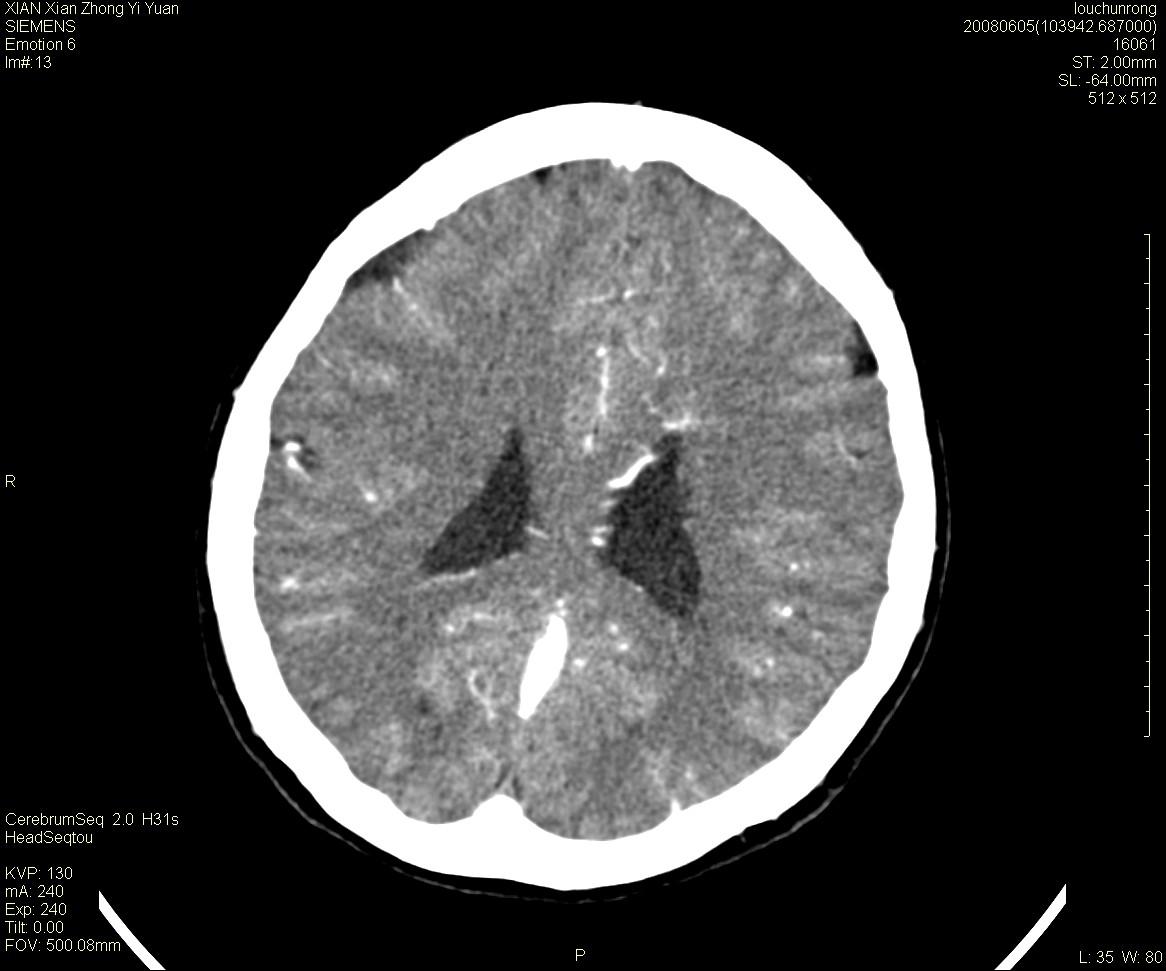

标题: CT13860:F52Y,,头外伤致头晕半天,以前无不适。 [打印本页]

标题: CT13860:F52Y,,头外伤致头晕半天,以前无不适。

层厚2mm。

左侧侧室内血管异常增粗,考虑血管变异或血管瘤可能,余未见异常

中线附近、枕叶近枕骨处及脑内多发点条状强化影,考虑血管异常?

大脑大静脉池内的密度不均,双侧脑室增宽,我看右异常这块。战友们看看